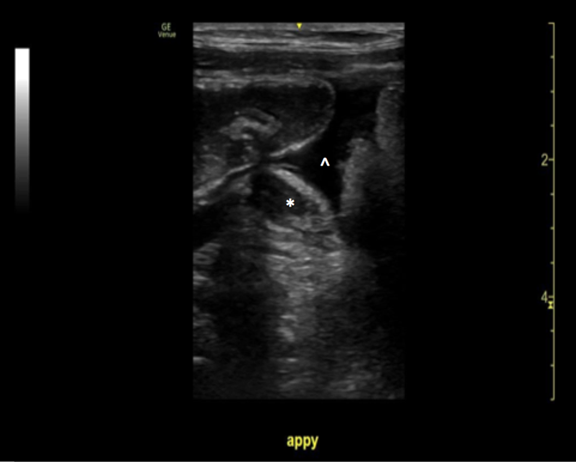

When appendicitis is present, the appendix will measure greater than 6 mm from outer wall to outer wall, with a wall thickness greater than 3 mm and lack compressibility. (Images 1, 8, and 9) (Remember, you may want to do these measurements after you have obtained your images, given your patient a high five and a sticker, and stepped aside to perform measurements on the machine.) An inflamed appendix can demonstrate a “ring of fire” with enhanced color flow. Secondary findings you may see include: an appendicolith, (Image 1), periappendiceal free fluid (Image 10), a target sign (Image 1), enlarged mesenteric lymph nodes, thickening and hyperechogenicity of the overlying peritoneum (Image 8), dilated and hypoactive small bowel, and thickening of the apical cecal pole.

Image 10. POCUS showing a dilated, non-compressible appendix (*) with periappendiceal fluid (^)